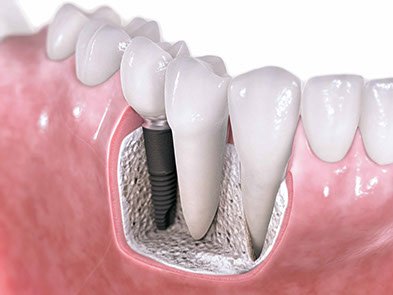

Diş İmplantları, eksik olan dişlerin yerine, çene kemiğine yerleştirilen titanyumdan yapılmış vidalardır. İmplantlar, küçük bir cerrahi işlemle çene kemiğine yerleştirilir. Bu işlemden sonra üç ay gibi kısa bir sürede tamamen çene kemiğine tutunur. Bu tutunma sonrası implant gerçek bir diş kökünün yerini alarak üzerine yapılacak protezi taşımaya hazır hale gelir.

İmplantlar; çene kemiğinde tek diş eksikliğinde, birden fazla diş eksikliğinde ve ağızda hiç diş olmadığı durumlarda uygulanmaktadır.

Çene kemiğinin yeterli kalınlıkta ve yükseklikte olduğu durumlarda implant hemen yapılabilir. Çene kemiğinin yeterli olmadığı durumlarda ise bu bölgeye çeşitli işlemler uygulanarak kemik implanta uygun hale getirilir. Hastaların operasyon sonrası ağız hijyenine dikkat etmeleri gerekmektedir.